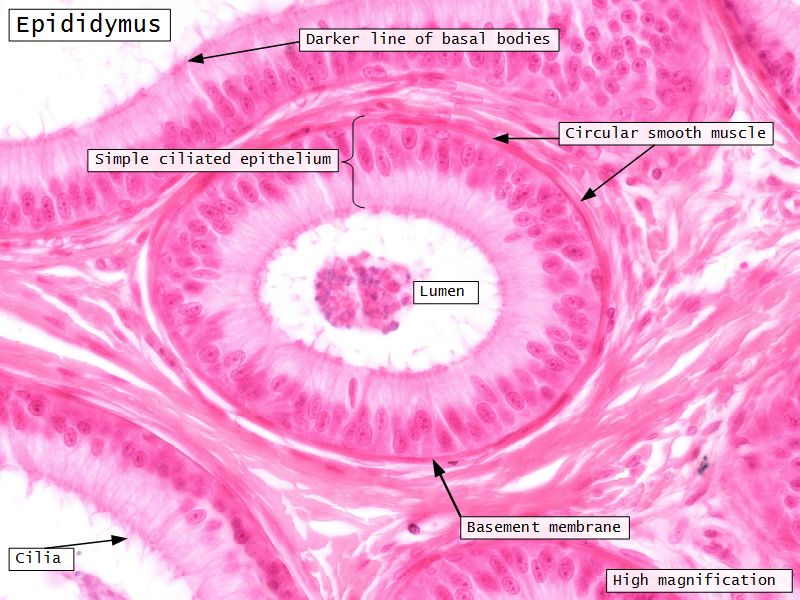

Epididymus

- Long convoluted duct

- With fibrous covering

- Inside visceral layer of tunica vaginalis testis

Epididymus

- Simple ciliated columnar epithelium

- Tall ciliated cells

- Elongated nuclei away from BM

- Low absorptive cells

- Spherical nuclei close to BM

- Surrounded circular smooth muscle